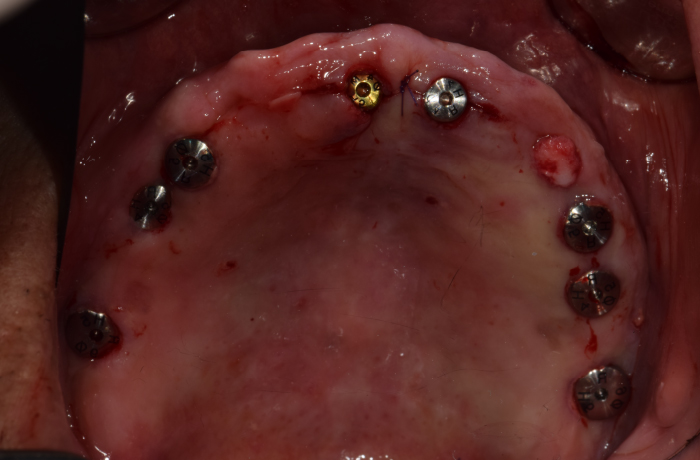

즉시 식립 임플란트 전후 사례

• 식립 전

식립 후